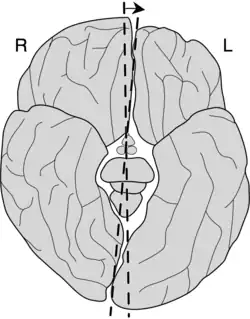

Das Großhirn besteht aus zwei stark gefurchten Halbkugeln (Hemisphären), die durch einen tiefen Einschnitt – die Hirnlängsfurche (Fissura longitudinalis) – voneinander getrennt sind. Die Verbindung zwischen den beiden Hemisphären wird durch einen dicken Nervenstrang, den so genannten Balken (Corpus callosum), hergestellt.